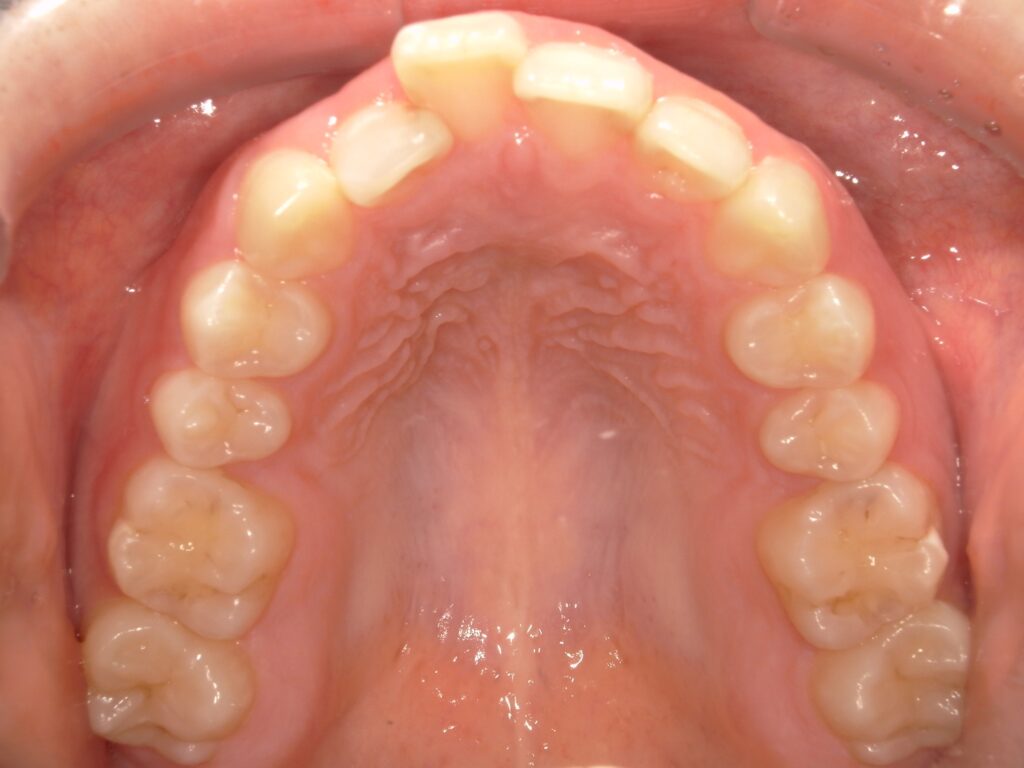

ガタつき / かみ合わせ

- 20代女性

- 主訴:ガタつきを綺麗にしたい

- 矯正方法:インビザラインの非抜歯矯正

- 治療期間:8ヶ月

- 治療費:710,000円

- その他ご要望:絶対に歯を抜きたくない、マウスピースを早く受け取りたい、分割払いご希望。

- 詳しくはこちら

Before

After

ご相談内容 ガタつきが気になると20代女性からのご相談 現状と治療方針 前歯のガタつきが見られます。他にも左側の奥歯が噛めていない状態にもあります。歯と歯の間にわずかなスペースを作る治療計画で矯正を行いました。 治療結果 ガタつきと噛み合わせを8ヶ月で改善できました。 振り返り 今回の患者様は噛み合わせの違和感はなかったものの、矯正治療の結果、奥歯で噛めるようになって初めて噛める感覚を知ったと喜ばれていました。また、絶対に抜歯をしたくないという希望も叶い安心して治療を進めることができました。また、マウスピースを早く受け取って早く始めたいというご希望もあったため、他院で先に矯正を始めていたご友人よりも早く終わらせることができたことに驚かれていました。 リスク・副作用 マウスピースの装着時間を守っていただけないと矯正治療に時間がかかり、場合によっては治療がうまく進まない可能性があります。